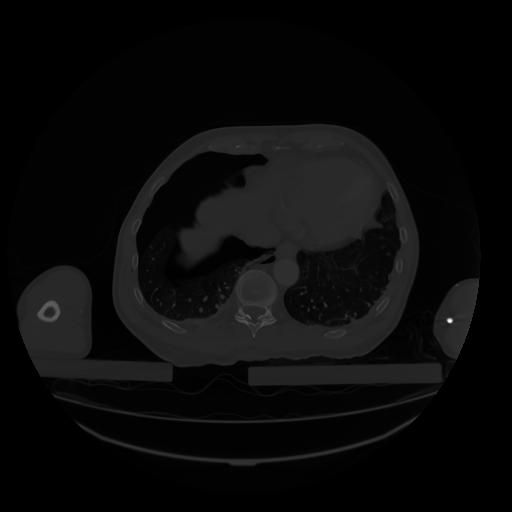

28 CUERPO,CE,Vol,2.0,CUERPO,,